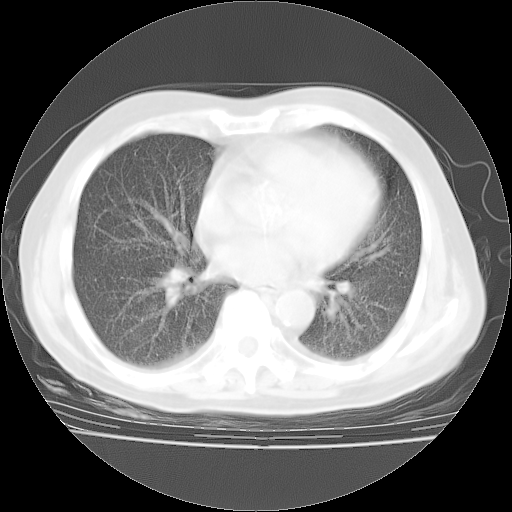

4月28日肺部CT——再次出现类似去年5月9日——磨玻璃样、间有“粟粒样”改变。